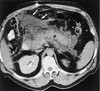

What pathology is seen here? Label A-D

Hepatocellular Carcinoma (HPC) -Multiphase study A: Non contrast: Mass is hypodense B: Arterial phase: Aorta bright, tumour enhanced, non uniform enhancement (mish mash) C: Portal venous phase D: Delayed phase